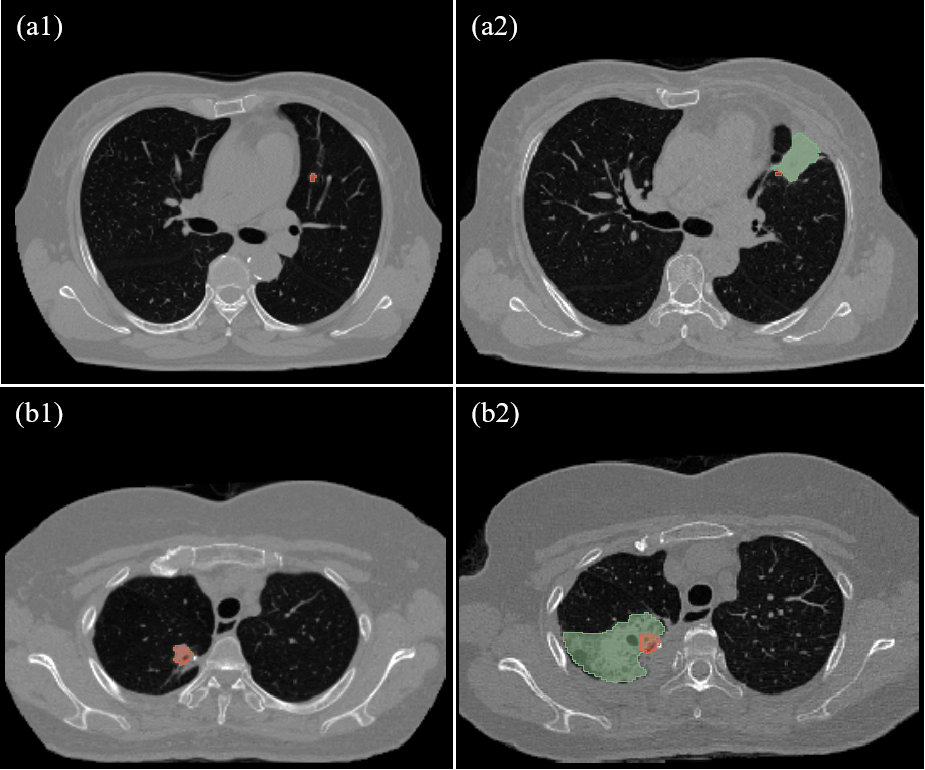

Figure 6: Illustration of the two special cases. (a1) and (b1) represent the preoperative CT images of two cases, with the tumor areas indicated in red. (a2) and (b2) represent the corresponding postoperative CT images, where the green areas denote the treatment regions and the red areas represent the registered tumor areas.

Notably, our experiments identified several outlier data points among cases classified as over-ablation (AES index value of 1) by doctors on immediate postoperative images, our system predicted an AES index value significantly less than 0, approaching -1, indicating potential under-ablation and possible therapeutic failure. Two such cases are illustrated in Fig. 6. Both cases have small tumor areas and large ablation areas, which led doctors to believe the ablation surgery was successful. However, As observed in (a2) and (b2) of Fig. 6, the registered tumor areas (red) are not included in the large ablation areas (green), indicating under-ablation. This is also objectively confirmed by medical records, which revealed that one patient was identified as under-ablated during the one-month follow-up, while another patient was identified as under-ablated during the six-month follow-up and subsequently underwent another ablation procedure.